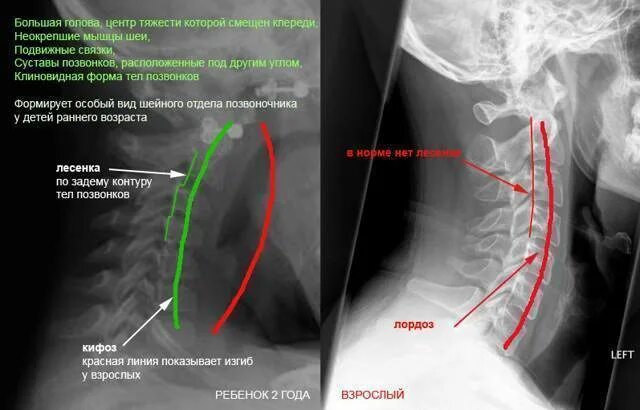

Нестабильность сегмента с3